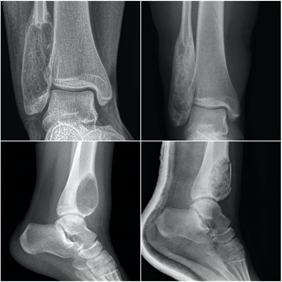

Siempre debemos estar atentos a los síntomas que nos refieren los pacientes, el tiempo de evolución y la respuesta a los tratamientos realizados. En los estudios de radiografías debemos igualmente observar con detenimiento cualquier alteración del hueso que se diferencie de los patrones radiológicos normales, con fin de detectar las anomalías óseas e iniciar el estudio y los tratamientos de una forma precoz y adecuada, muchas veces junto a un equipo multidisciplinar. En las radiografías debemos prestar atención a la localización de la lesión, su forma, tamaño, matriz ósea, la existencia de reacción perióstica o afectación de partes blandas.

En pacientes con historia previa de carcinoma, ante la presencia de dolor óseo debemos contemplar siempre la posibilidad de diseminación ósea metastásica. Las revisiones rutinarias de oncología suelen realizar rastreos periódicos a descartar posibles diseminaciones. En ocasiones la metástasis se descubre como una fractura, en ocasiones ante un traumatismo leve o incluso de forma espontánea. En otras ocasiones se detectan como microfracturas en los estudios oncológicos de gammagrafía o resonancia, tras un inicio insidioso de dolor en la zona.

El fémur es la localización principal, con predominio de la zona de la cadera. Otras localizaciones son la columna vertebral, la pelvis, los huesos planos y el húmero. En la espalda el dolor suele estar presente antes que los cambios radiográficos, mientras que cuando el dolor se localiza en los huesos largos suelen ya existir lesiones con riesgo de fractura.

Ante la sospecha de una fractura patológica de origen metastático debemos tener un enfoque multidiscilplinar, tanto traumatológico como oncológico, con fin de realizar tanto el tratamiento específico de la fractura como el estadiaje oncológico.